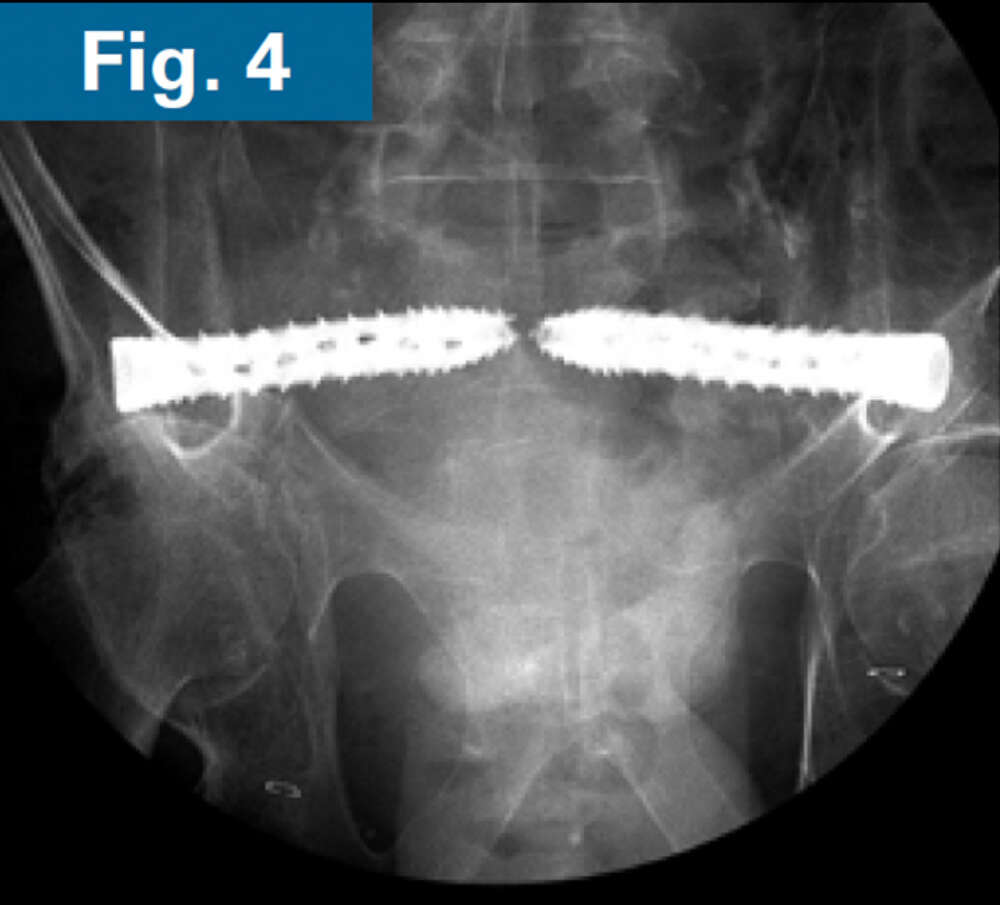

His pelvic abscesses were debrided and washed (lateral window) and antibiotic beads were placed followed by percutaneous placement of bilateral ilio-sacral style S1 implants. Intraoperative CT scan was performed after placement of 3.2 mm guidewires to confirm safe path of placement for iFuse TORQ implants in the setting of poor visualization of the foramen (Fig. 3). Bilateral 13.5mm iFuse TORQ implants were placed and the patient was allowed weightbearing as tolerated for activities of daily living at his home (Fig. 4).

Firoozabadi - spinopelvic dissociation - 4 Firoozabadi - spinopelvic dissociation - 4